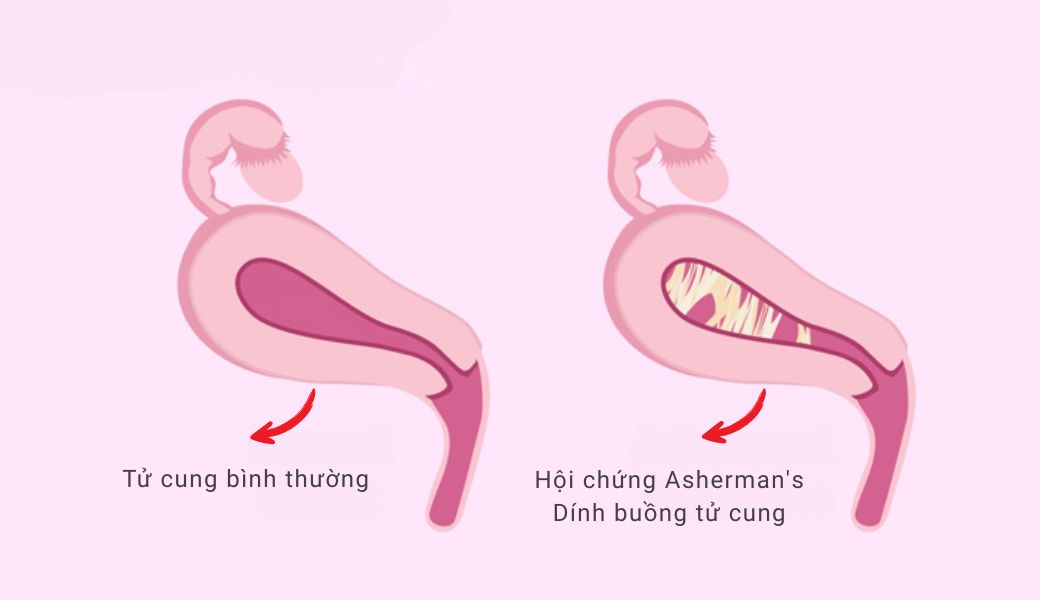

Dính buồng tử cung, hay còn gọi là hội chứng Asherman, là tình trạng hình thành các dải sẹo hoặc mô liên kết bất thường bên trong buồng tử cung. Những dải dính này có thể là màng mỏng hoặc dải sẹo dày, chia buồng tử cung thành nhiều ngăn nhỏ.

Trong điều kiện bình thường, thành trong của tử cung được phủ bởi lớp nội mạc tử cung mềm mại. Khi bị tổn thương, lớp nội mạc này có thể lành sẹo và dính lại với nhau, tạo thành những cầu nối bất thường.